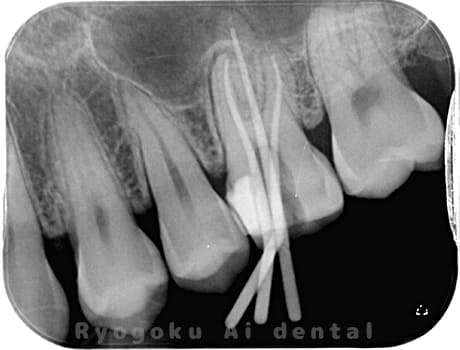

Case03

-

- 原因

- 急性化膿性根尖性歯周炎

- 治療期間

- 2ヶ月

- 治療内容

- マイクロエンド

- 治療費用

- 121,000円

黙っていても痛みが出るとのことで来院した患者様です。本治療は症状もあるため、抜髄治療をマイクロエンドで行いました。